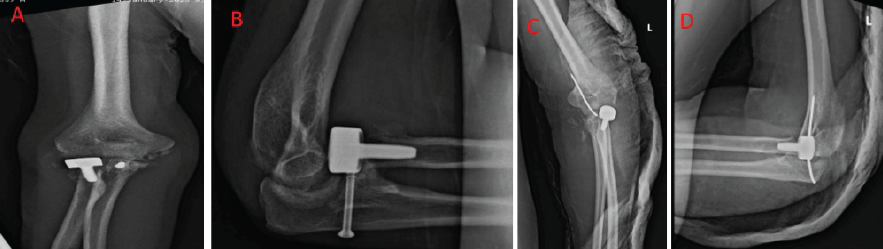

Considering the polytrauma status and complexity of injuries, the patient was managed according to the “life over limb” principle. Initial surgical intervention followed a damage control orthopedics strategy. The patient first underwent articular reconstruction of the distal femur along with application of a knee-spanning external fixator for stabilization. Closed reduction and temporary stabilization of both elbows were performed using a K-wire and slab support. Wound debridement was also carried out at this stage to minimize the risk of infection. Following these initial procedures, the patient required intensive care unit stabilization for 15 days before further definitive surgeries could be planned. In the 3rd week, spinal fusion from D11 to L2 was performed for the L1 burst fracture. Two weeks later, after soft tissue recovery, the left distal femur was fixed with a locking plate, and the right calcaneum and medial malleolus were stabilized using cannulated screws in a single session. In the 5th week, the elbows were managed in a staged manner, as the patient’s debilitated condition rendered him unfit for simultaneous and prolonged surgical procedures. The patient was operated on in a supine position with the arm resting over the hand table. After induction of general anesthesia, an examination under anesthesia was performed before initiating the procedure. Antibiotics were given, and the tourniquet was applied. For the left elbow, the Kocher approach was used for radial head replacement, and the anteromedial approach was taken to fix the coronoid fracture with 1 fiber wire through the suture pull-out technique. Elbow stability was assessed both clinically and under an image intensifier. The left elbow was found to be unstable, and therefore, 1 ulno-humeral K-wire was inserted. Later that week, the right elbow was also addressed. For the right side, both bone forearm fractures were first fixed with open reduction and internal fixation with a locking compression plate. After this, radial head replacement and coronoid fixation with 1 cancellous cannulated screw were done through the Kocher approach (Fig. 3). The right elbow was found to be stable; the total surgical time taken was 160 min for the right side and 130 min on the left side.

Figure 3: Immediate post-operative X-rays of right elbow (a) anteroposterior and (b) lateral view and left elbow (c) anteroposterior and (d) lateral view